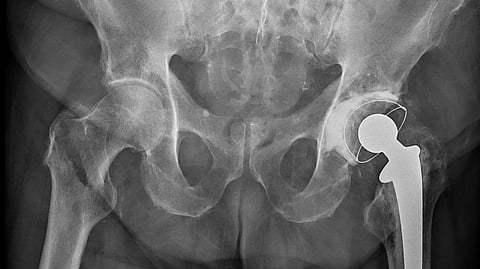

Her tumble caused extensive damage to her hip bone, and she was taken by her family to the hospital in an emergency. "Surgery at this age carries significant risks and complications, but she has responded well to the procedure," said Dr. Anurag Dhaker, who led the surgical team. "We implanted a prosthetic component to repair the fractured area, which involved replacing the hip joint ball. She will regain her ability to walk," he added.

Given the potential complications of prolonged immobility, doctors proceeded with the surgery rather than leaving the fracture untreated. Without medical intervention, she could have been confined to bed, increasing the risk of respiratory problems, bedsores, urinary tract infections, and pneumonia. Dr. Dhaker said that hip fractures are especially dangerous for older patients, usually resulting from falls and exacerbated by osteoporosis, a weakening of the bones. Injuries like this can have serious implications for health, mobility, and overall quality of life. Her age makes this case stand out. Studies have shown that despite the successful treatment of hip fractures, the fractures have a long-term impact on mobility and health, generally affecting mortality rates in older individuals.